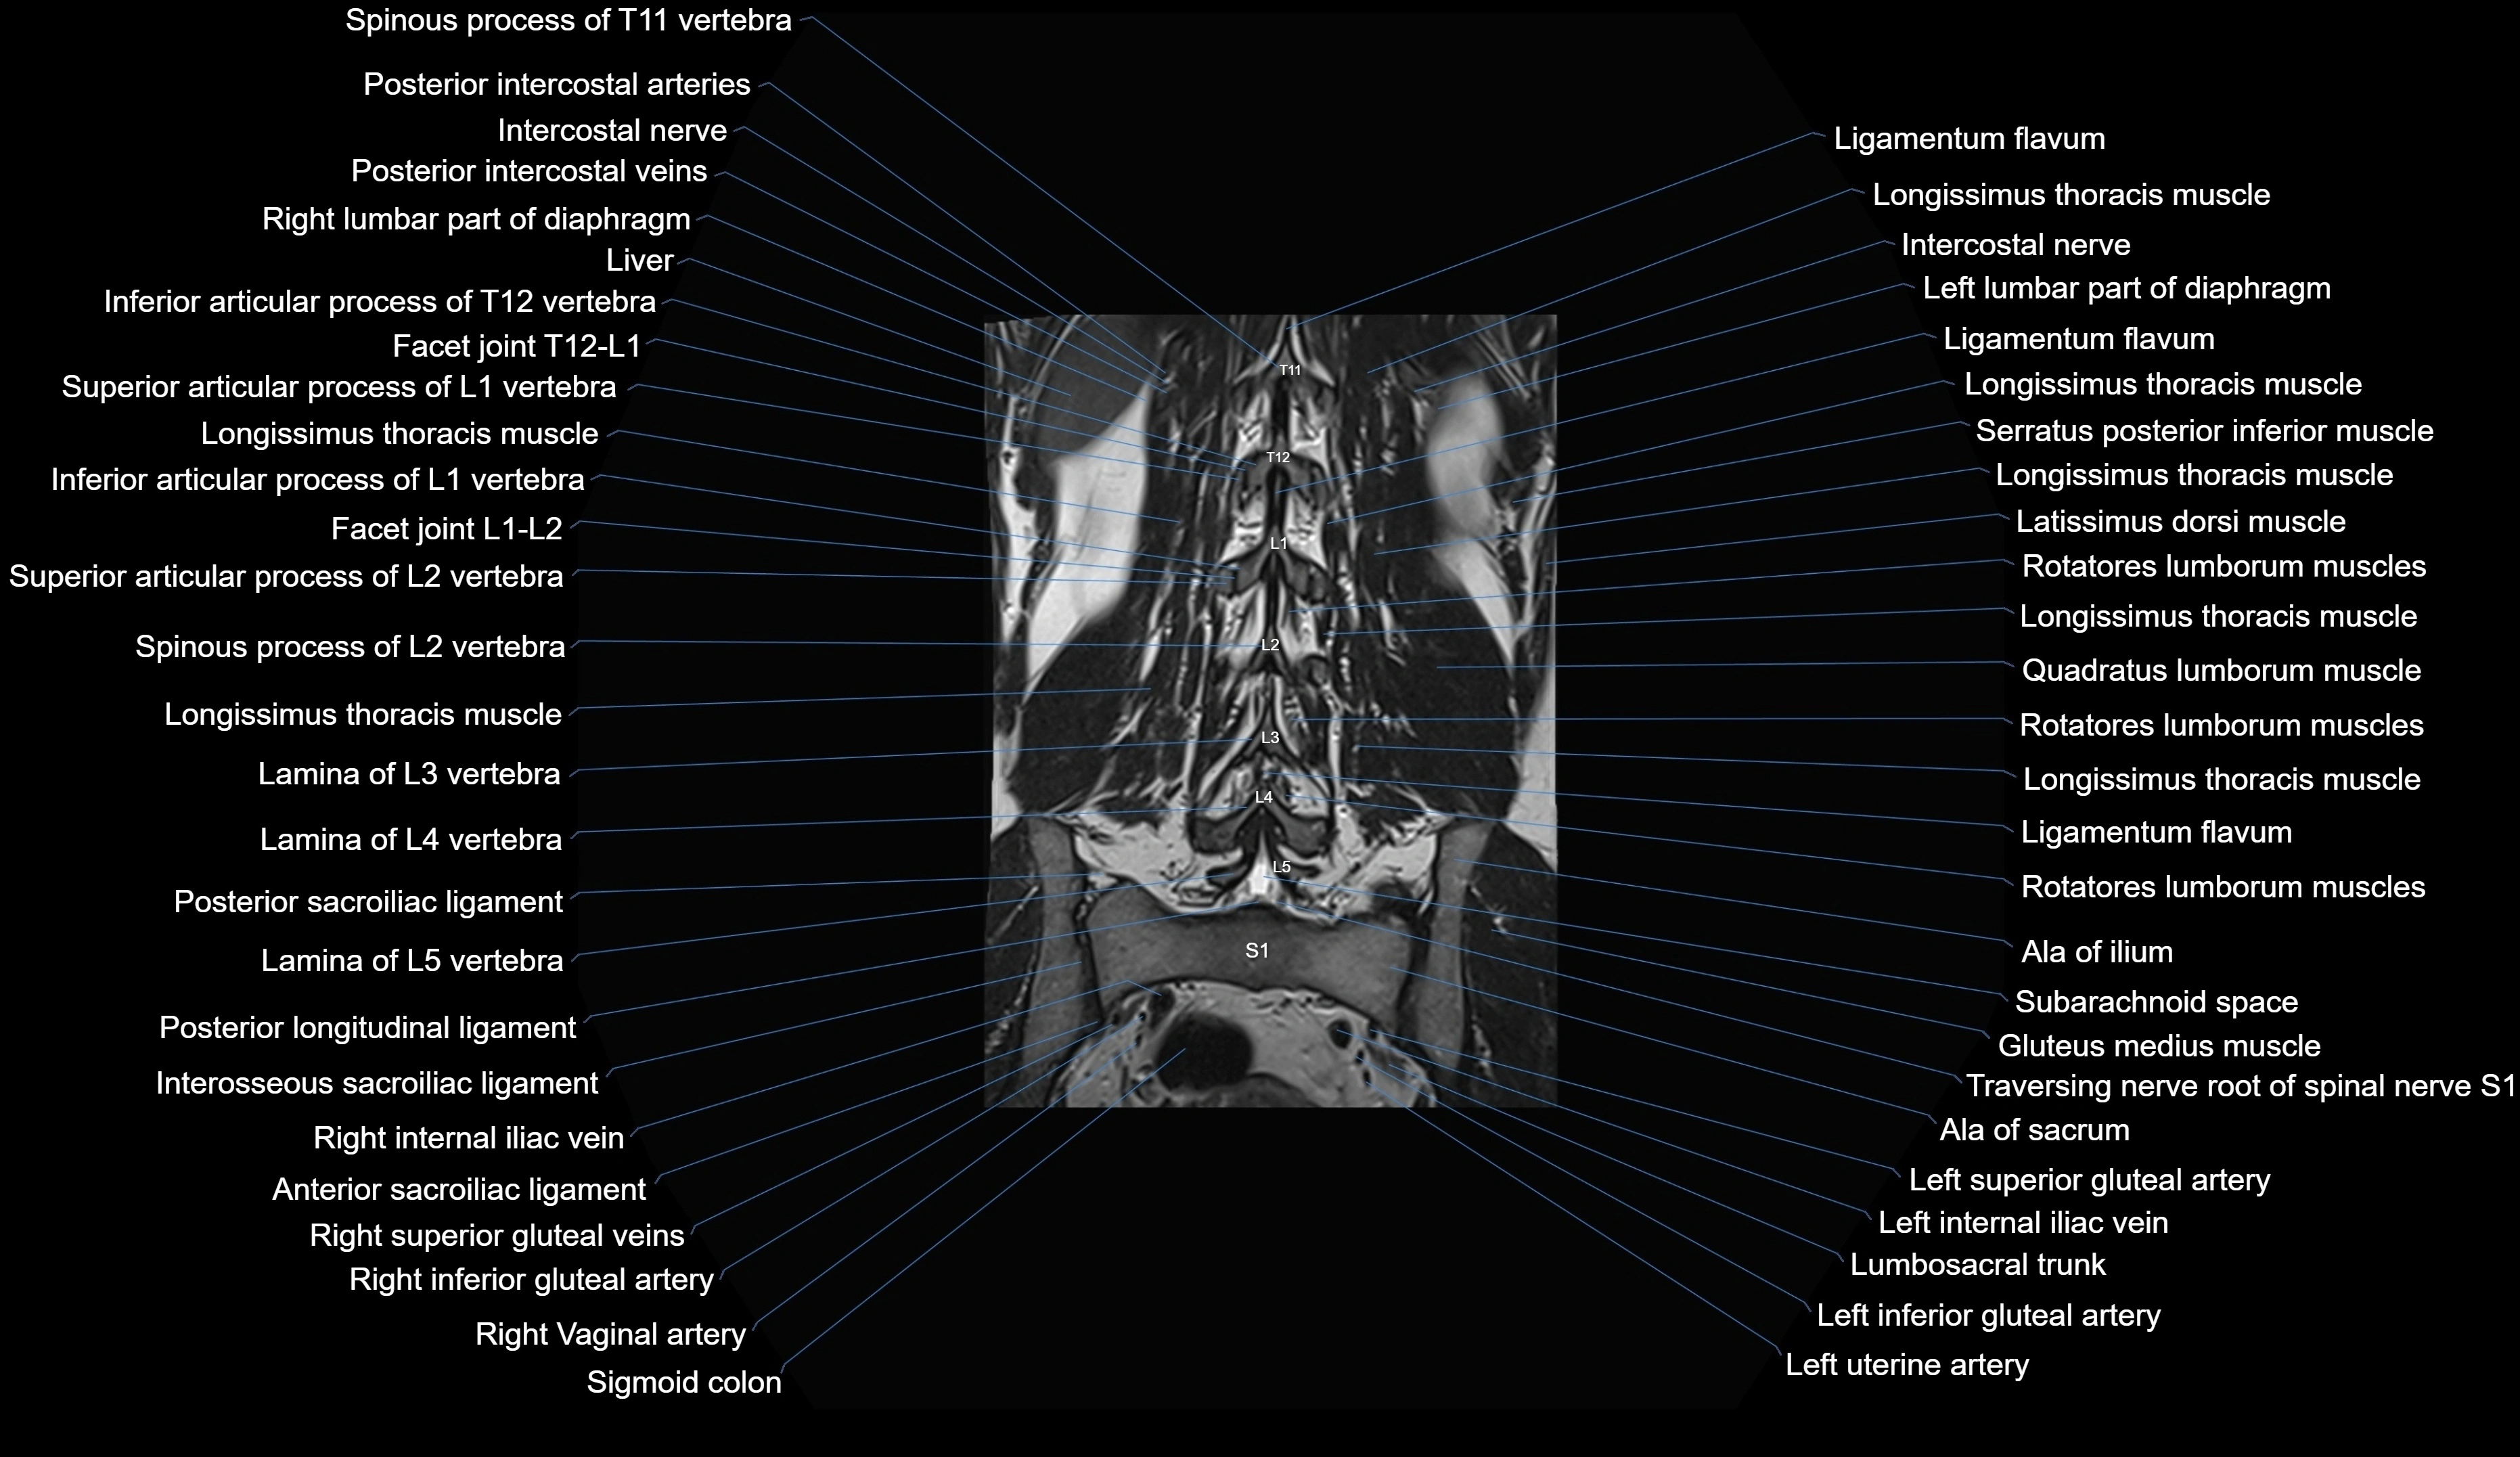

MRI images